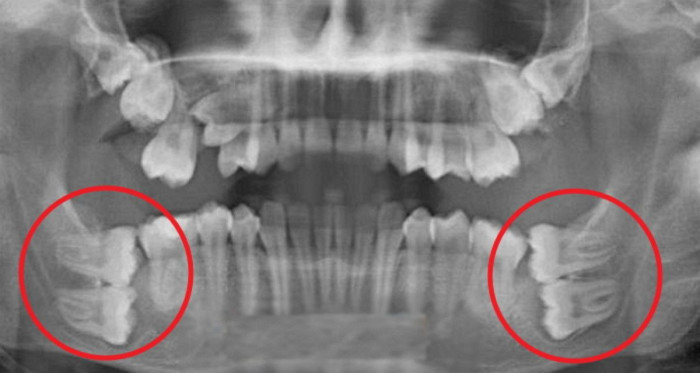

매복사랑니 4개 발치했습니다^^

죄인이네요...... 사랑니 덕에 어금니도 잃었습니다......

아 사진 뭐임 진짜 혈압 확 오르네

???? 와 첫번째 사진은.. 오마이갓..

첫번째 사진….이가 왜저렇게 많으신가요…?